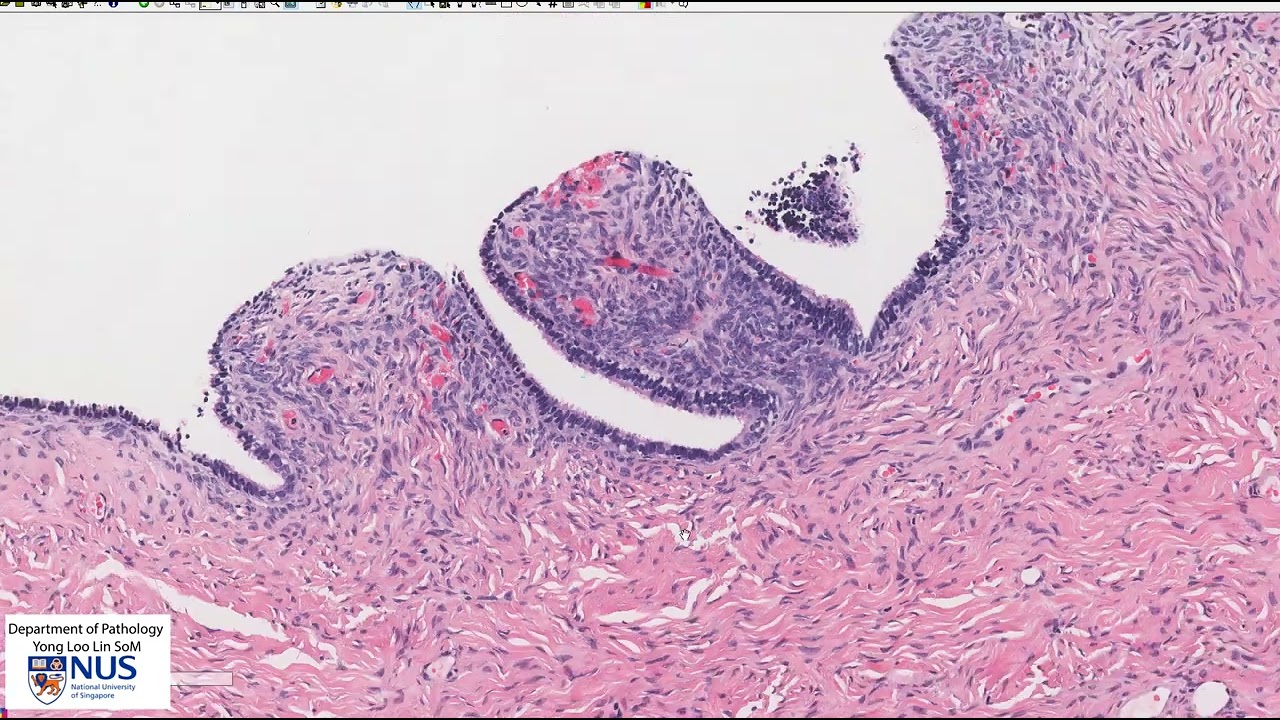

Ovary: Serous cystadenoma Microscopy - Talking slide

Описание: Demonstration of the salient histologic features of serous cystadenoma of the ovary.